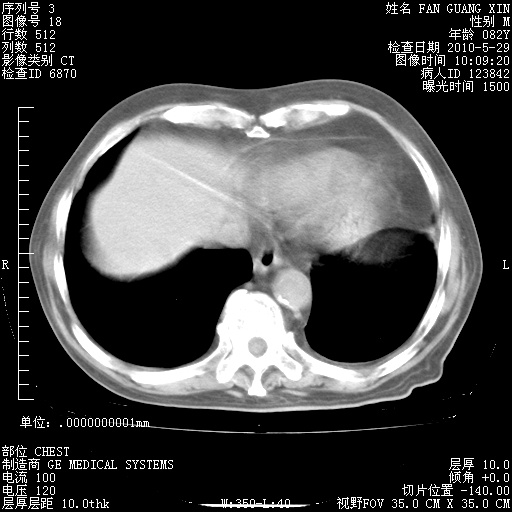

再治疗10天后的肺部CT 纵膈窗

阅读此次胸部CT,肺间质渗出性改变较入院时有吸收。目前从体温、白细胞、中性分叶明显增高,肯定存在细菌感染(发生医院感染哦,若无消化道及泌尿系统等感染的依据,肺部感染可能大)。若你院头孢哌酮舒巴坦钠耐药率较高,同意你的方案,若48小时体温仍高,可考虑使用碳青霉稀类抗菌药物,同时可予超声雾化、注意滴数时加大液体量。白蛋白33.30g/L较低哦,需加强营养等支持治疗。